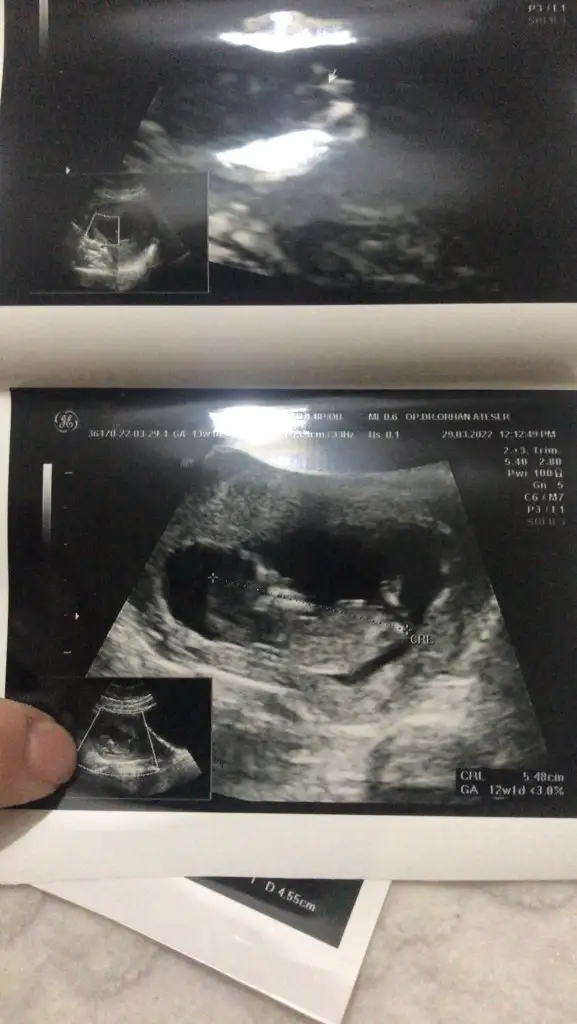

Kızlar 13 haftalık bebeğimin fotoğrafı. Sizce cinsiyeti nedir?